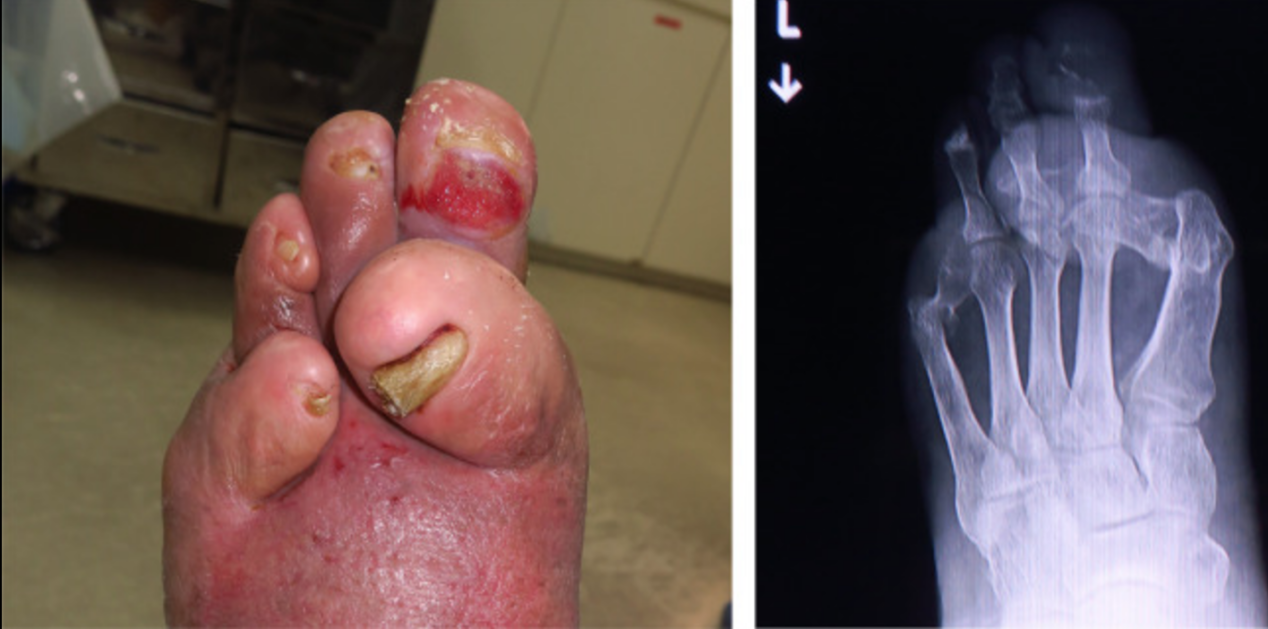

一名73岁的患者的第二趾有一个持续六月的糖尿病足部溃疡,愈合欠佳(图1-左)。患者糖尿病史数十年,自行停止了糖尿病治疗。经检查,患者无发热及体力降低。患者第二跖骨头区域有局部感染,左脚溃疡暴露了第二个近端指间关节(PIPJ)。溃疡周围的皮肤红肿,指向溃疡处第二跖骨指骨关节(MTPJ)的足底表面。踝臂指数为1.18/1.26(右/左),皮肤灌注压为97/75 mmHg(背侧/足底)。通过一个简单的负重X线图像观察左脚,第二近端指骨和中指骨有破坏(图1-右)。第一和第五指的MTPJ脱位(图1-右侧)。伤口、缺血和足部感染(WIfI)分类为W2、I1、fI 2、F 0。

图1